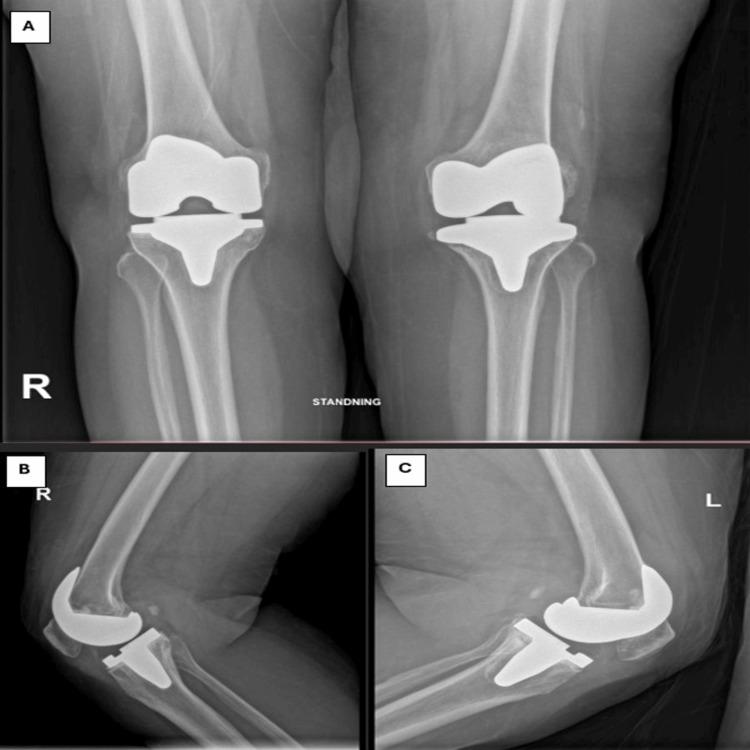

Total knee arthroplasty (TKA) is a common procedure for managing severe knee osteoarthritis. However, component loosening continues to be a common issue, frequently requiring revision surgery. Although the medial parapatellar (MPP) approach is commonly used due to the broad access it provides, it may disrupt the extensor mechanism and reduce blood flow to the patella. We present a case of a 62-year-old woman who required revision TKA (RTKA) on the left knee due to tibial component loosening seven years after her initial surgery, which had been performed via the MPP approach. We have used the midvastus (MV) approach to preserve the quadriceps tendon. This case highlights the MV approach as a viable alternative in RTKA, offering adequate exposure while minimizing soft tissue damage.

全膝关节置换术(TKA)是治疗重度膝关节骨关节炎的常见手术。然而,假体松动仍然是一个常见问题,常常需要进行翻修手术。尽管内侧髌旁(MPP)入路因其提供的广泛视野而被广泛使用,但它可能会破坏伸膝机制并减少髌骨的血液供应。我们报告一例62岁女性病例,该患者在初次手术(采用MPP入路)七年后,因胫骨假体松动需要对左膝进行翻修全膝关节置换术(RTKA)。我们采用股中肌(MV)入路以保留股四头肌肌腱。该病例突出了MV入路在RTKA中作为一种可行替代方法的优势,它能提供足够的视野,同时将软组织损伤降至最低。